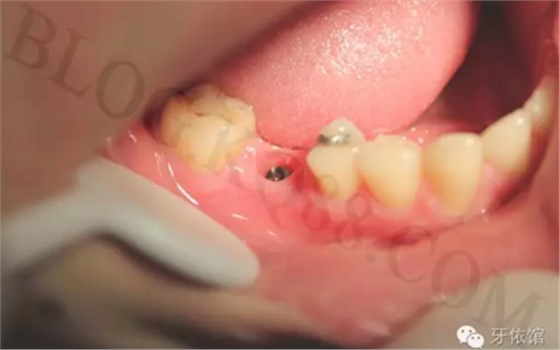

術(shù)后三個(gè)月的口內(nèi)照片。

卸下愈合基臺,可見袖口干凈整潔。